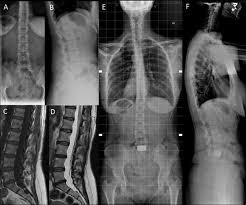

Deciding On Surgery For Cervical Degenerative Disc Disease